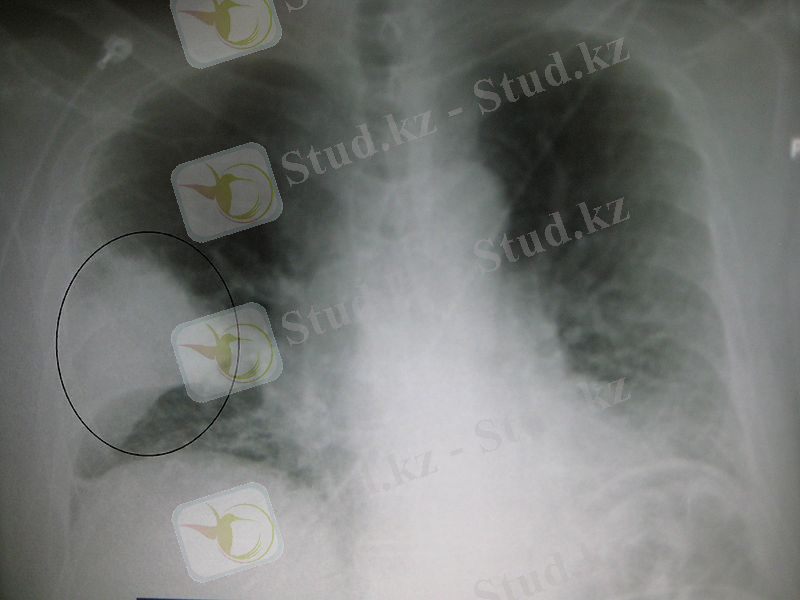

Пневмония

Пневмония (гр. pneumon - өкпе), өкпе қабынуы - өкпе тінінің қабынуынан немесе басқа аурулардың асқынуынан болатын өкпенің жұқпалы ауруы. Ол көбіне қызылша, көкжөтел, тұмау, бронхит, демікпе сияқты тыныс ауруларын немесе әсіресе жас балалар мен қарт адамдарда болатын қатаң аурулардан кейін пайда болады. Сонымен қатар ол СПИД-пен ауырған кезде де болуы мүмкін.

Ауруды әр түрлі вирустар (аденовирус, риновирус), бактериялар (пневмококк, стафилококк, стрептококк) қоздырады. Аурудың дамуына дененің қатты мұздауы, ауыр жұмыс пен жүйкелік-психик. күш түсу, улану, т. б. факторлар әсер етеді.

Этиологиясы

1. Бактериялар (пневмококк -70-96%, алтын сары стафилакокк- 0, 5-5 %, Фридлиндер пневмобацилласы -3-8 %, көкшіл- ірің таяқшасы- 3-8 %, стрептакокк -1-4% ) . 2. Вирустар ( А2 -грипінің вирусы - 77, 1%, Б- грипінің вирусы -16, 4%, С- грипінің вирусы 1%, аденовирус - 3, 6%, парагрипп вирусы- 1, 2%, тыныс синцитий вирусы-1, 5%) . 3. Орнитоз -0, 6% . 4. Микоплазма- 0, 5-1, 5% . 5. Риккетсиялар, патогендік гриптер . 6. Аллергия. 7. Табиғи және химиялық факторлар: салқын тию, күйік, сәуле, улар.